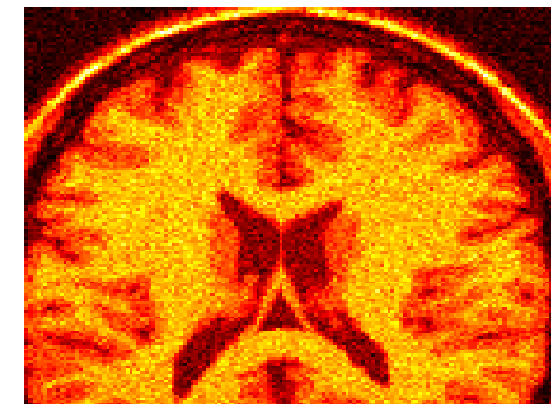

4.2 Magnetic resonance imaging

Gaussian noise images typically arise within the framework of magnetic resonance imaging (MRI). The challenge in this case consists in training the machines so that a clearer image is obtained. The magnetic resonance images seem to be the natural choice for our methodology, since a training set of images is often at hand.

For such a training set we consider the solution of problem (40). In Figure 2 the noisy images together with the final optimized ones for a brain scan are shown. For this experiments a mesh step size of was considered. The Tikhonov regularization parameter took the value , while the Huber regularization parameter was chosen as .

With this values, the optimal parameter value for the MRI image with 3% of noise was . When the noise in the image was of 9%, the computed optimal weight was .